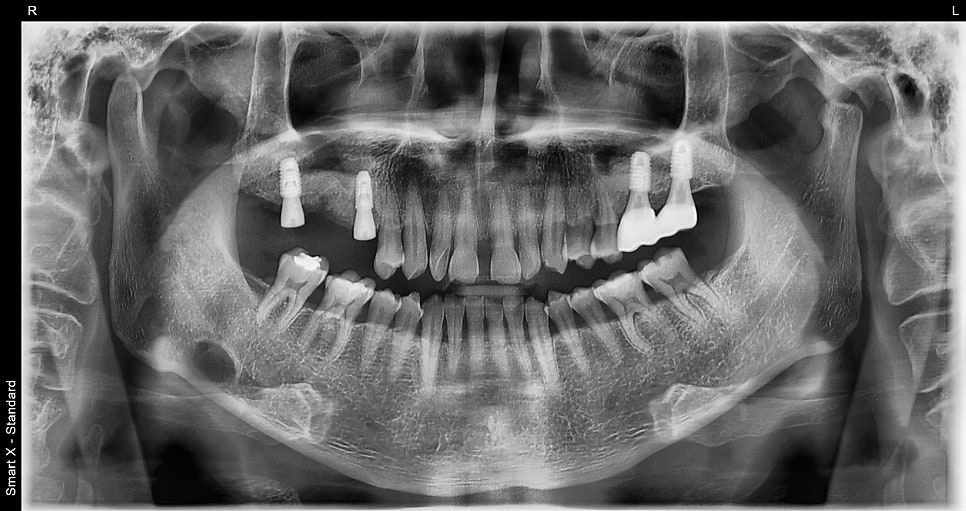

This panoramic X-ray shows the condition after the second surgery and completion of healing abutment connection.

The implant placement sites remained stable, and the progress after the first surgery was excellent, with no gum inflammation or complications.

Left photo: panoramic X-ray taken after the final prosthetic restoration was placed.

Right photo: intraoral photo after treatment was completed.

The prosthesis was made with zirconia material, resulting in a strong yet aesthetically pleasing finish with excellent harmony with the natural teeth.